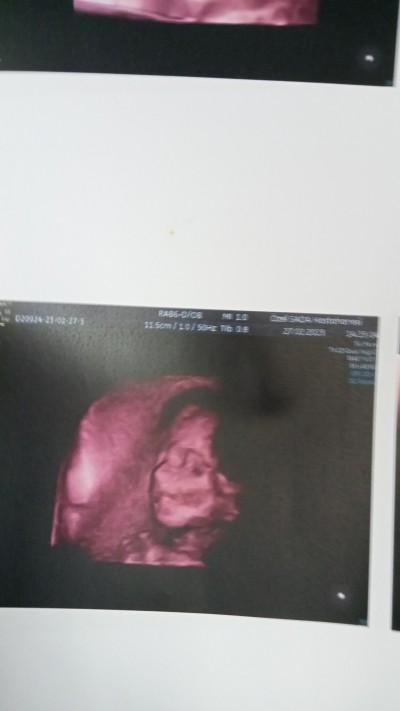

image